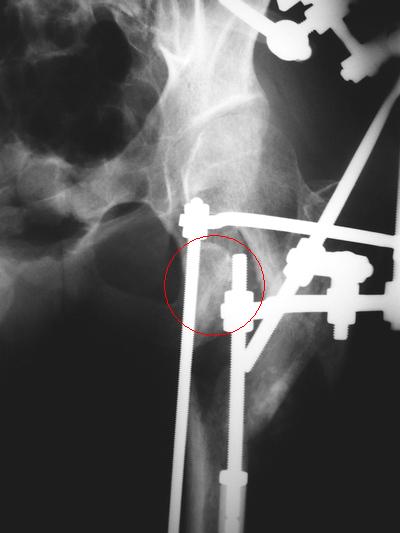

Девушка 21 года 02.10.07 г. пострадала в результате падения с высоты 4-го этажа при пожаре в одном из студенческих общежитий г. Москвы. Получила тяжелую сочетанную травму, в том числе закрытый оскольчатый чрез- и подвертельный перелом левой бедренной кости. Лечилась в одной из больниц столицы. Бедро было фиксировано при помощи скелетного вытяжения. Через полтора месяца после травмы переведена в институт им. Склифосовского. У больной имелись: поддиафрагмальный абсцесс, трахеопищеводный свищ, трахеостома, гастростома, несостоятельность швов раны передней брюшной стенки, укорочение левого бедра на 10 см (рентгенограммы при поступлении - рис 1.).

В середине декабря был наложен спицестержневой аппарат, с помощью которого к сегодняшнему удалось устранить укорочение бедра (рис. 2). В течение последних 4-х дней устраняем смещение дистального отломка бедренной кости по ширине. Раны на передней брюшной стенке почти зажили. Температура тела и лабораторные показатели нормальные. Планируем выполнить закрытый остеосинтез левой бедренной кости  удлиненным проксимальным бедренным штифтом производства фирмы "Остеомед".

Нас смущает, что малый вертел бедренной кости остается значительно смещенным проксимально и кнутри.